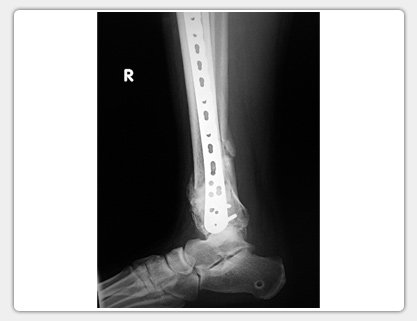

Synthetic Bone Substitute